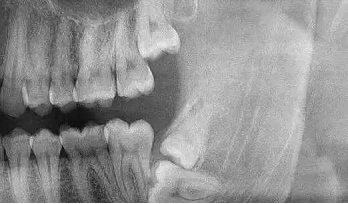

阻生牙(impacted teeth)是指部分萌出或完全不能萌出,且以后也不会自行萌出的牙。好发部位为下颌第三磨牙、上颌第三磨牙及上颌尖牙,其中阻生第三磨牙也叫做阻生智齿。

4、牙列不齐:智齿萌出运动的推动力常是造成牙齿拥挤和排列不整齐的主要原因之一。